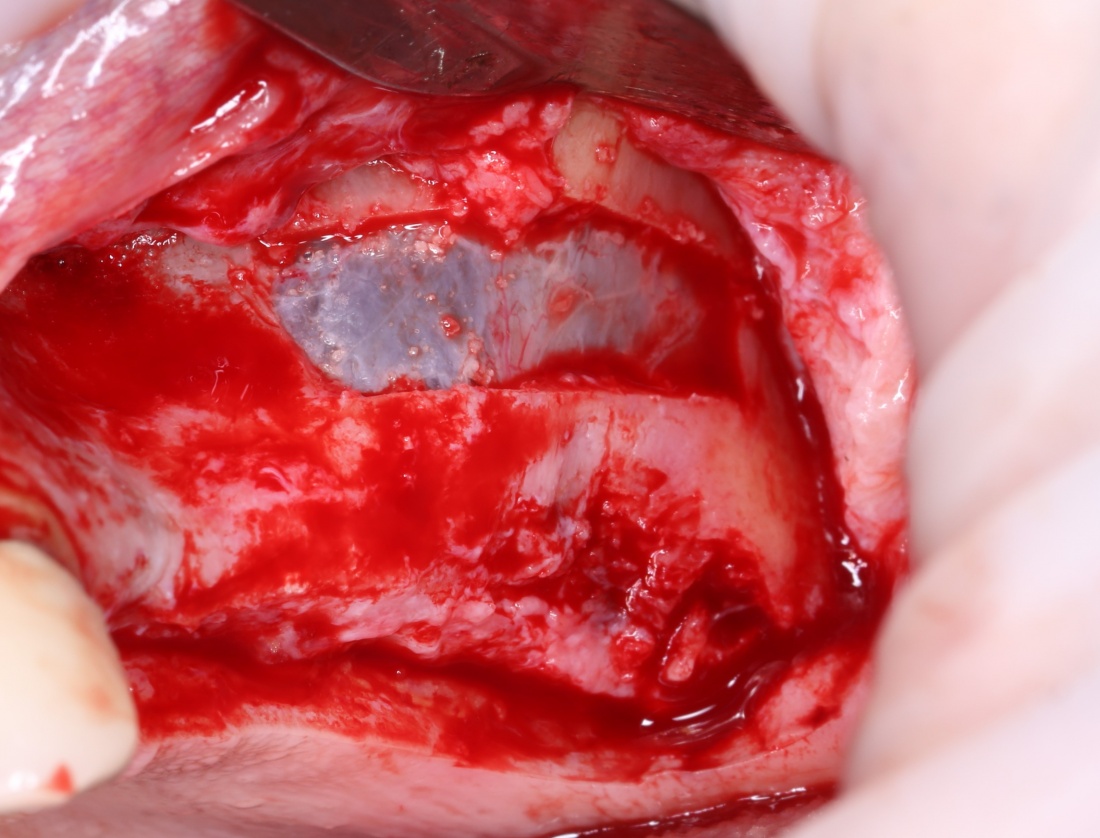

Я же в своей практике для создания доступа использую ультразвук, а именно — электрический пьезохирургический аппарат VarioSurg (NSK). Он позволяет делать очень красивый и практичный доступ любой формы:

- после создания доступа получается костный фрагмент, который мы можем использовать по-разному (для закрытия перфорации, костной пластики,

сварить холодец или чего-нибудь еще)

- можно создавать большие доступы и закрывать их получившимся костный фрагментом, легко обходить септы, шипы и перегородки дна верхнечелюстной полости

- сам процесс создания доступа получается более контролируемым.